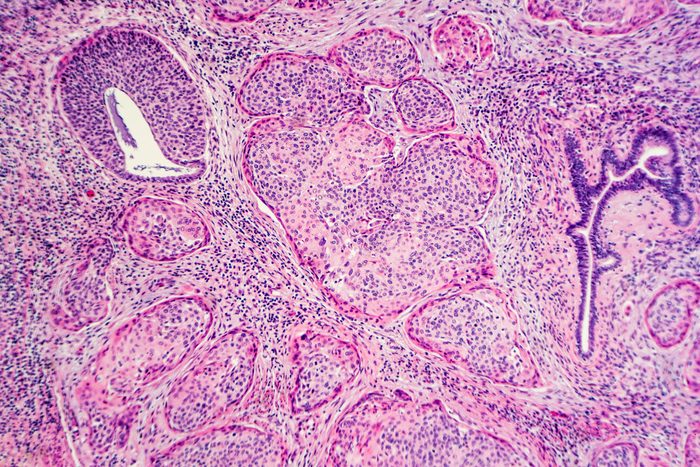

Papanicolaou (Pap) smear tests, which involve swabbing a sample from the cervix to detect precancerous cells, can find changes in the cervix before cancer develops—or catch the cancer early when it’s easier to cure. Since Pap tests were introduced in the 1950s, the incidence of invasive cervical cancer declined dramatically: Cases and death rates declined by more than 60 percent since the 1960s, according to the National Cancer Institute. Unfortunately, the decline has tapered off over the last 15 years.

A computer algorithm that analyzes digital images of a woman’s cervix can accurately identify precancerous changes that require medical attention. In a study published in JNCI: Journal of the National Cancer Institute, the researchers report that computer analysis of the cervical images was better at identifying precancer than a human expert reviewer of Pap tests under the microscope (cytology). The new method may be valuable in areas where there is a shortage of health care providers.